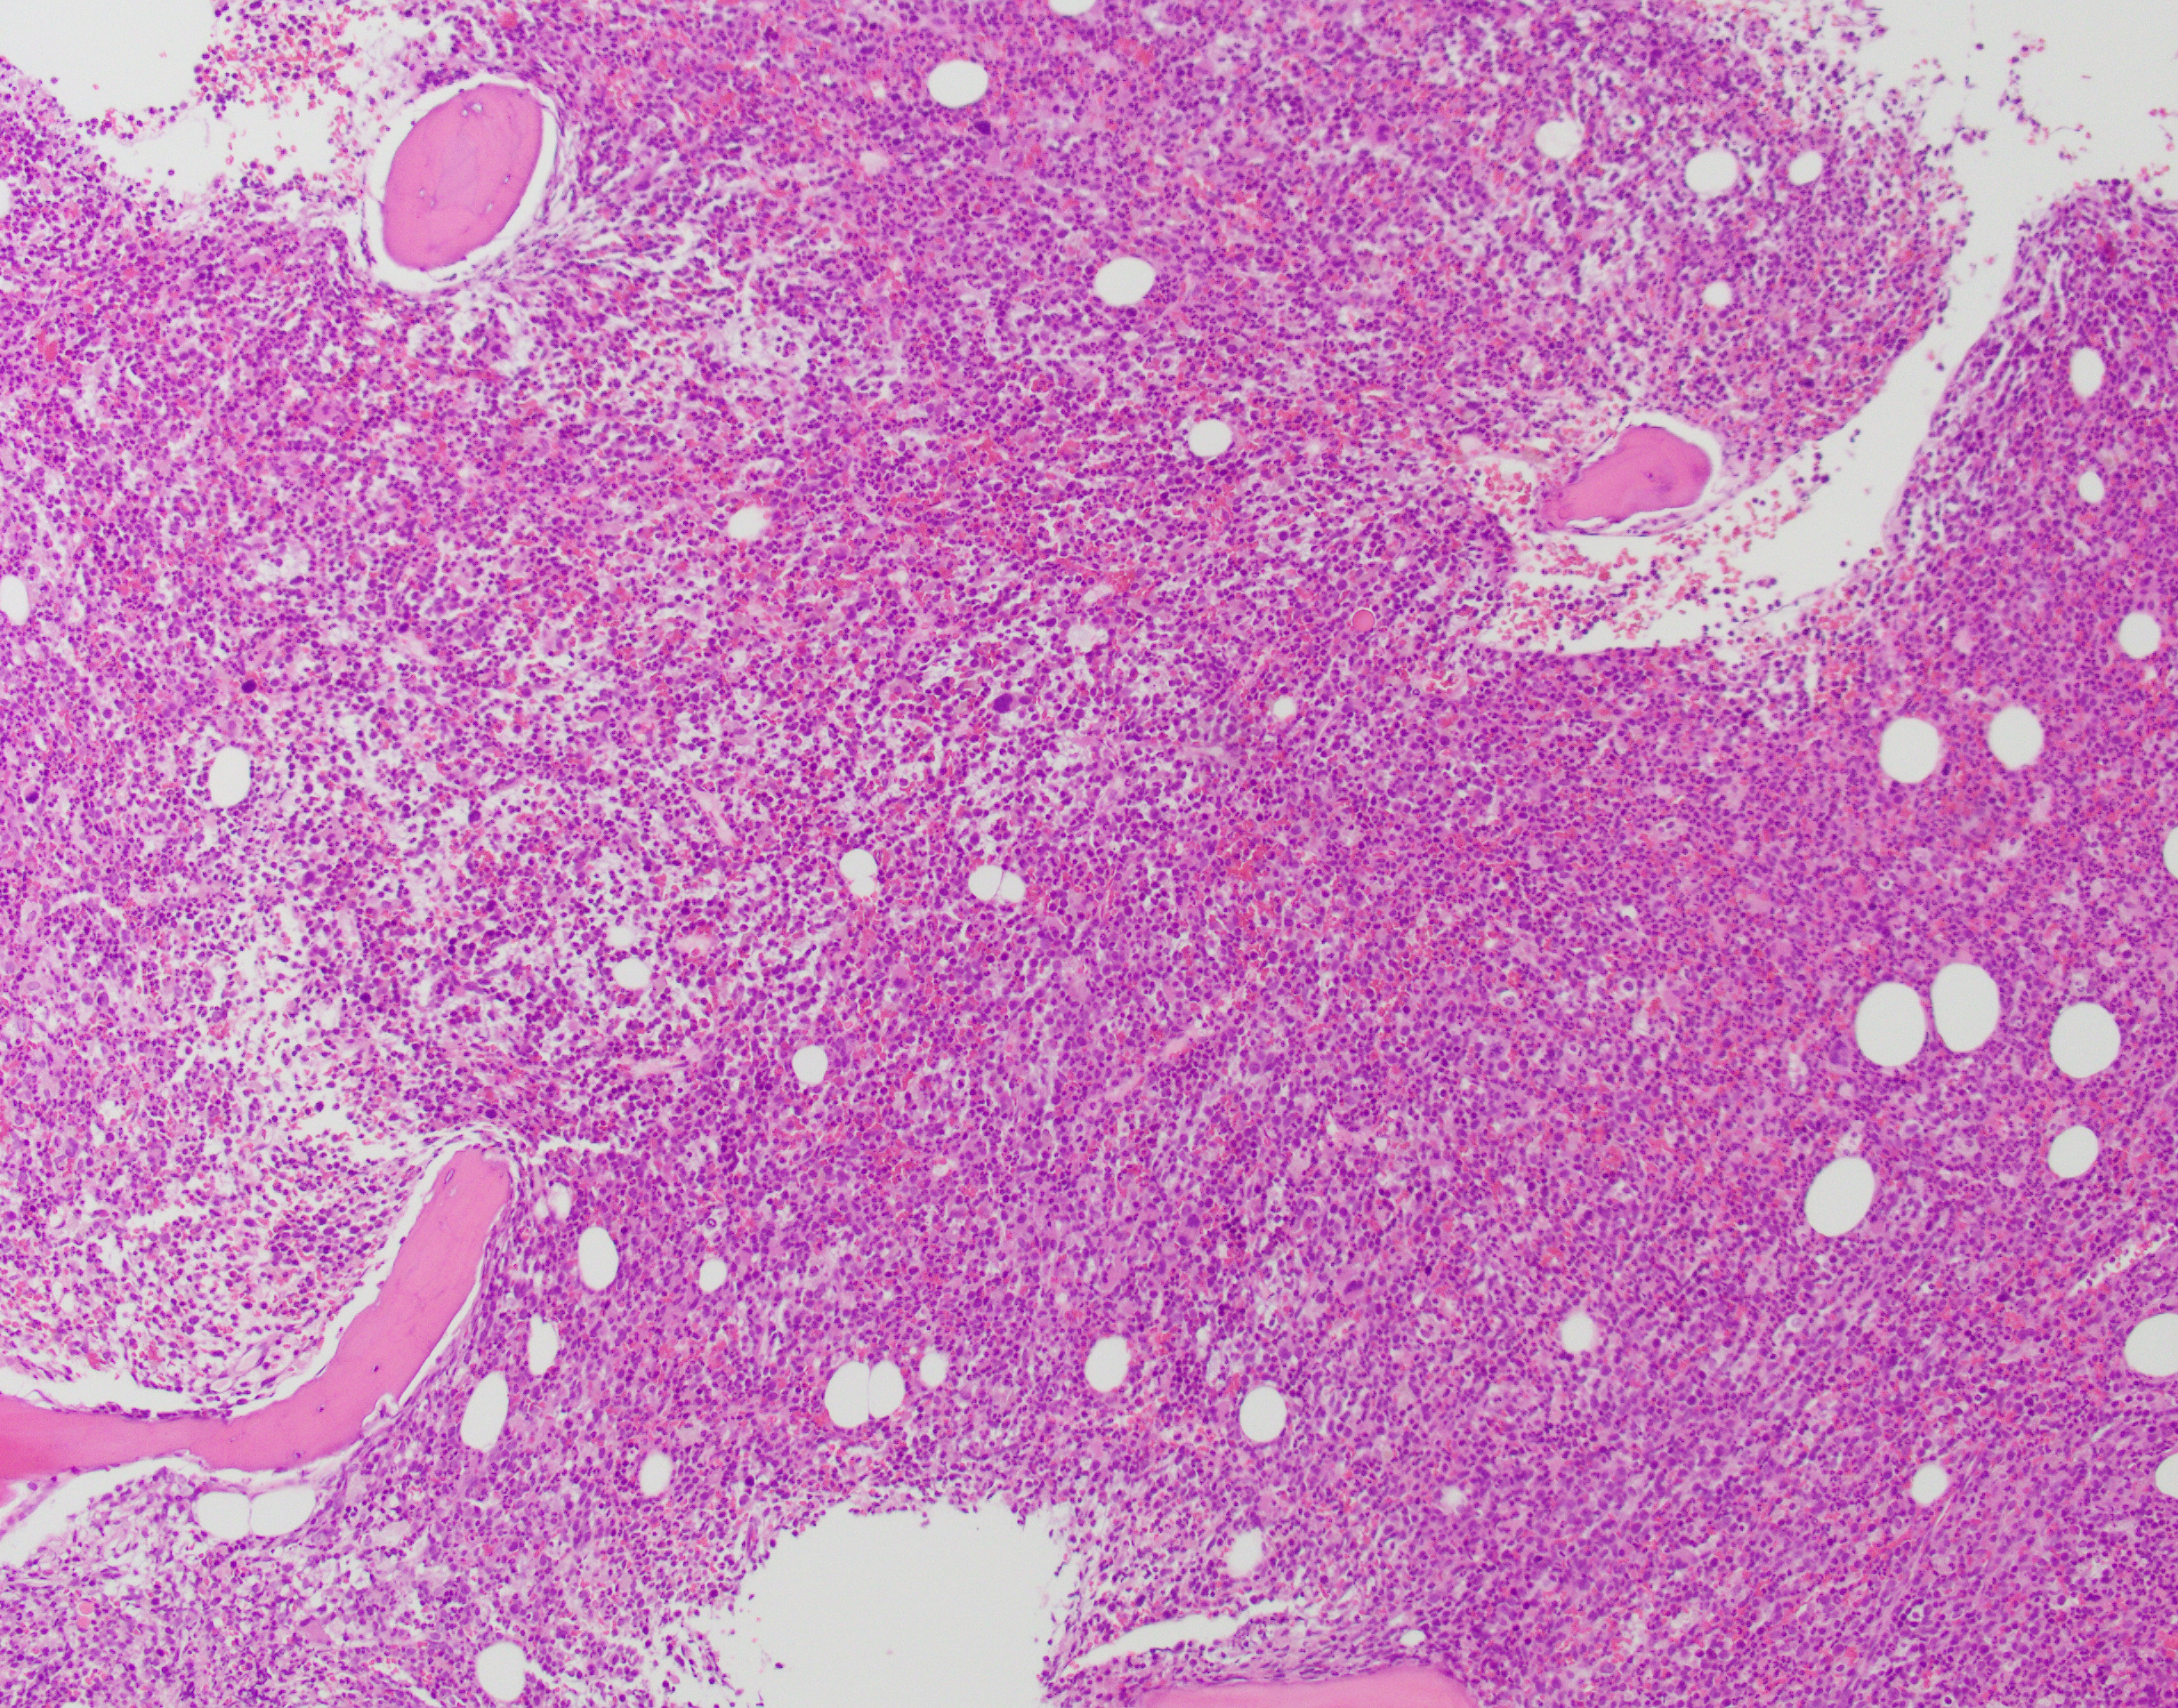

The patient is a 76-year-old male with anemia (Hgb 8.6) and thrombocytopenia (15,000/microliter). Of note, serum copper levels are low. Photomicrographs of the bone marrow aspirate and biopsy are provided.

The patient's bone marrow biopsy shows a hypercellular marrow with dysmegakaryopoiesis and no overt increase in blasts on routine stains. In a patient with cytopenias and this morphology, the diagnosis is unfortunately rarely straightforward. The differential diagnosis of entities that can cause morphologic dysplasia is long and includes infection, medications, autoimmune processes, nutritional deficiencies, and myeloid neoplasms. Follow-up of concurrent cytogenetic and molecular tests is essential for further classification; however, a normal karyotype does not fully rule out a myelodysplastic syndrome.